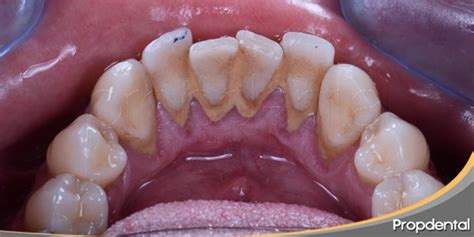

A diferencia de la placa que es una película incolora, el sarro presenta minerales siendo fácilmente visible si se localiza por encima de la línea de las encías. El indicador de sarro más común es observar un color marrón o amarillento en los dientes o encías. En general, el dentista puede detectar la presencia de sarro a simple vista mediante una exploración.

El sarro duro detrás de los dientes presenta inicialmente una coloración amarillenta que puede evolucionar hacia tonos marrones o incluso negros, dependiendo de factores como el tabaquismo, el consumo de té, café o ciertos alimentos.

La anatomía oral explica por qué el sarro duro detrás de los dientes inferiores es tan común. Las glándulas sublinguales y submandibulares, ubicadas debajo de la lengua, secretan constantemente saliva rica en minerales directamente hacia la superficie lingual de los incisivos inferiores. La superficie lingual de los dientes inferiores representa una de las zonas más desafiantes para mantener una higiene bucal adecuada.

La posición de la lengua, la limitada visibilidad durante el cepillado y la dificultad para maniobrar el cepillo en esta área contribuyen a una limpieza incompleta. Muchas personas concentran sus esfuerzos de higiene bucal en las superficies dentales más visibles, descuidando inadvertidamente las zonas posteriores y linguales.